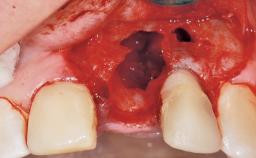

Immediate Flapless Placement of an Implant in a Maxillary Left Central Incisor Site

A 42-year-old female patient was referred to our clinic at the School of Dentistry of the University of São Paulo in November 2004, presenting a deficient restoration in the upper left central incisor. The clinical examination revealed no gingival retraction or any signs of gingival inflammation and, therefore, previous periodontal treatment was not considered. The patient presented a high lip line at full smile and a thin tissue biotype. This combination characterized a high-risk situation from an anatomic point of view, which required careful preoperative planning and cautious surgical execution.

Soft Tissue Anatomy Intact Defective